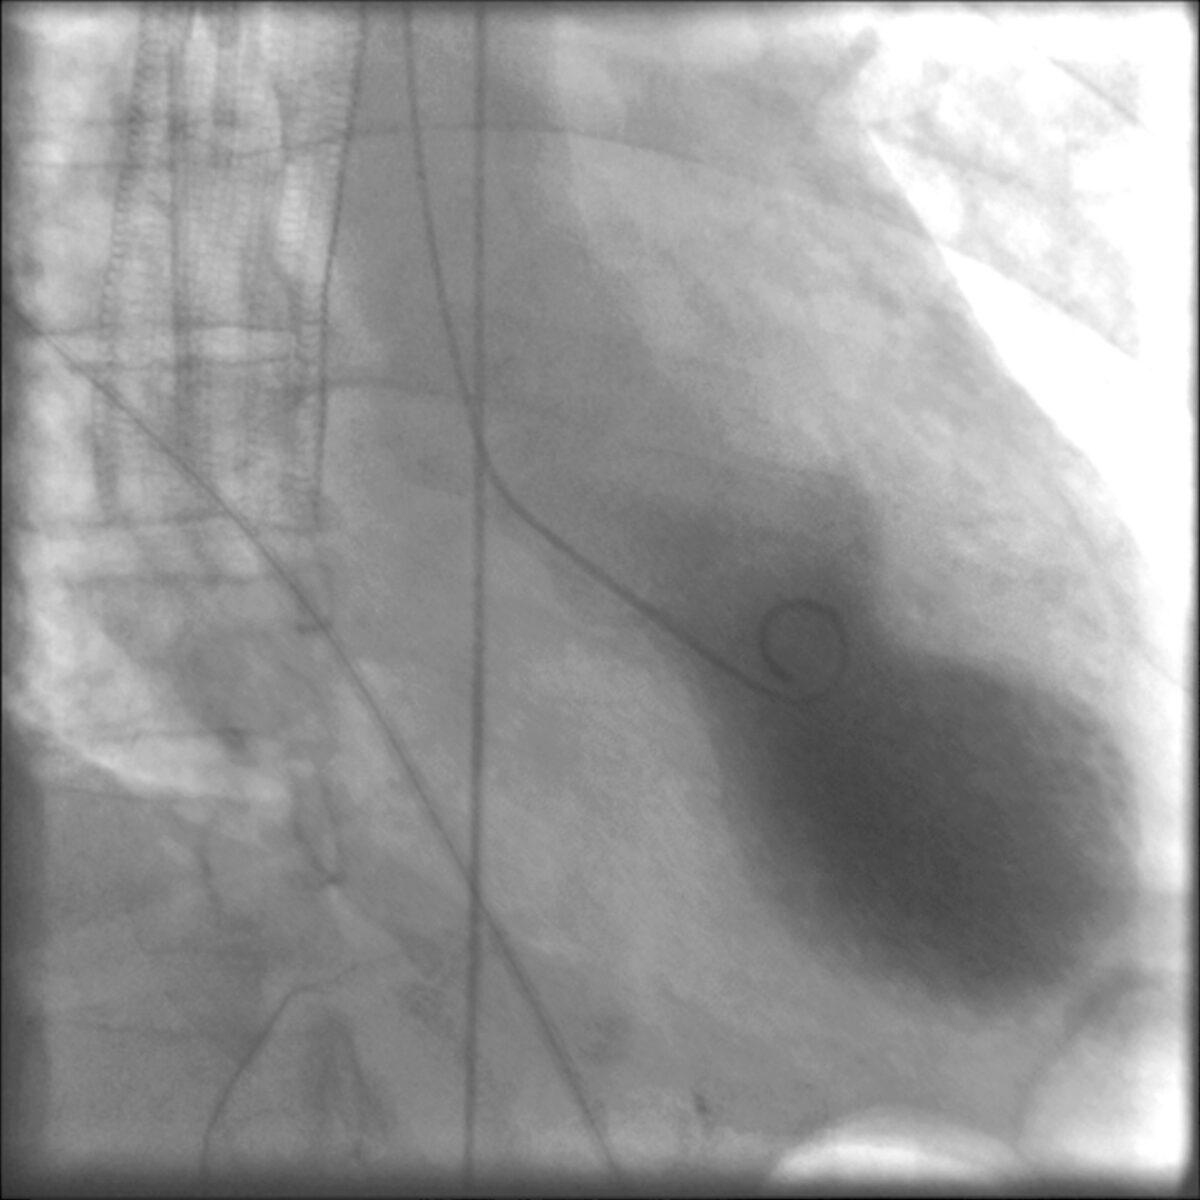

Angiografia coronária com estenose proximal grave da LAD

Angiografia coronária com estenose grave da artéria descendente anterior esquerda (LAD, pela sigla em inglês)

Imagem: “Coronary angiography showing a severe proximal LAD stenosis” por V. Parisi et al. Licença: CC BY 2.0